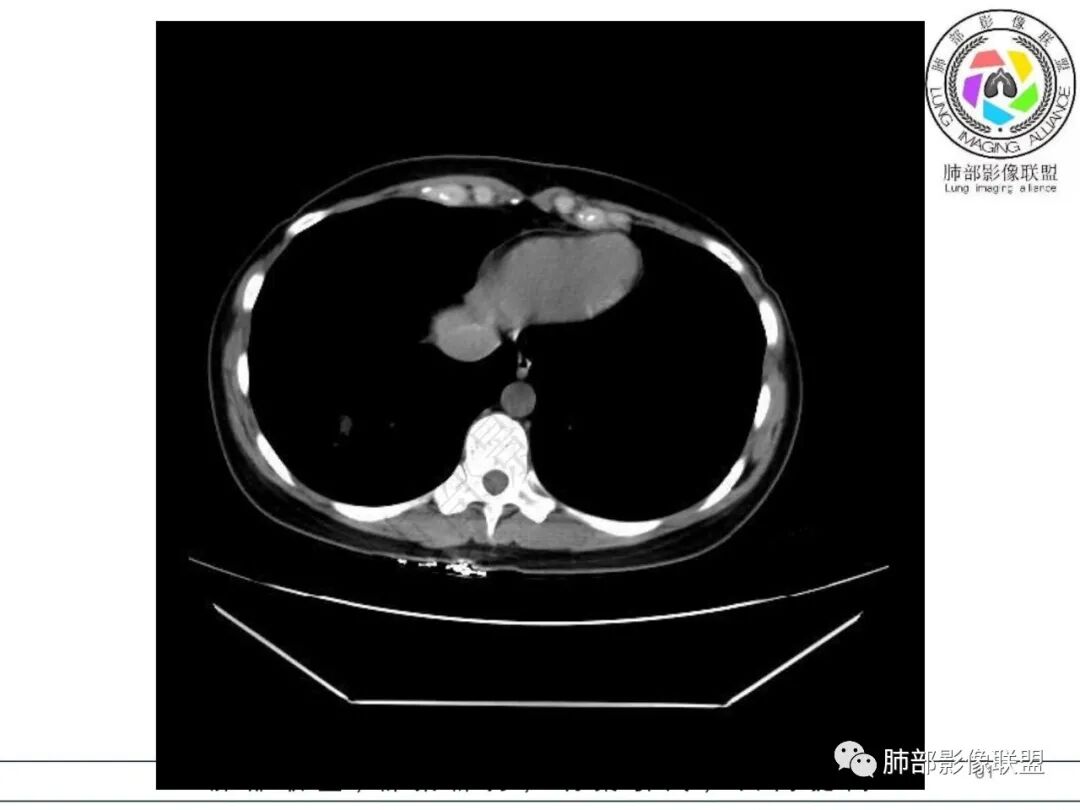

右肺下叶局限性实变影伴晕征。

后、外基底段实变

周围GGO边界不清

2.影像特征:右肺下叶局限性实变影伴晕征,边界不清,内部支气管尚通畅,实变区密实区边缘稍膨隆。符合炎性病灶特征。